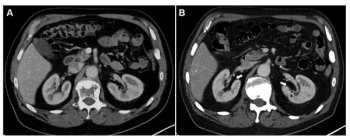

In patients who had at least four cycles of 177Lu-PSMA-I&T for mCRPC, new research shows that a 10 percent or greater decrease in total kidney volume on CT at six months has a 90 percent AUC for predicting estimated glomerular filtration rates (eGFRs) of 30 percent or greater at one year.